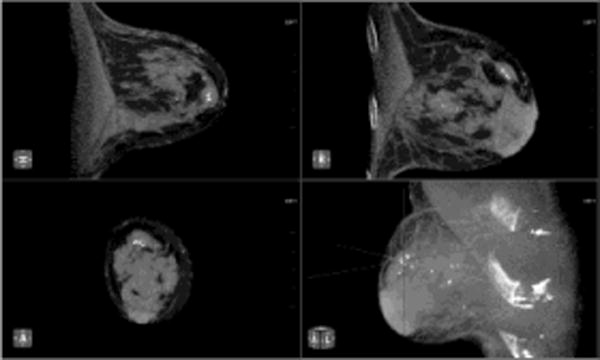

Fig. 3. Assessment of index lesion and extent of disease.

Patient presents with palpable mass in the right breast. Mammographic CC (A) and MLO (B) views demonstrate large irregular mass at the 12 o’clock position consistent with BIRADS-5:highly suspicious (white arrows). (c) Contrast enhanced CBCT was performed to evaluate extent of disease, which demonstrates the index lesion in exquisite detail (crosshairs). No satellite lesions or axillary adenopathy is identified.